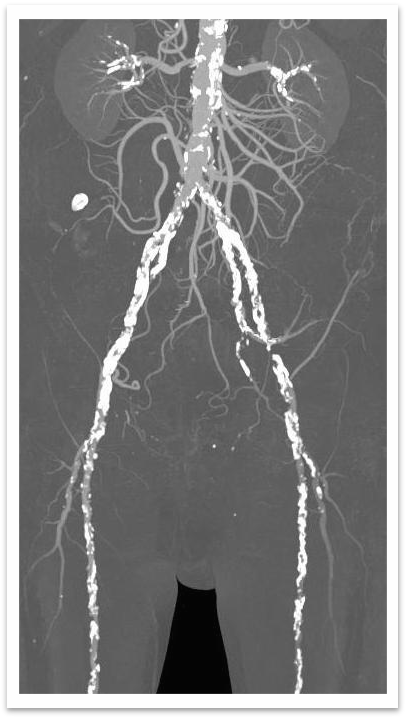

1.下肢动脉彩超:双侧股总-股浅动脉长段狭窄、左侧部分管腔不全闭塞;右侧胫前动脉管腔次全闭塞;左侧胫前动脉、双侧足背动脉管腔闭塞。

2.腹主动脉CTA:腹主动脉下段轻度狭窄,左侧髂总动脉管腔中-重度狭窄,左侧髂内动脉重度狭窄,左侧髂外动脉闭塞,左侧股总动脉以及股深动脉近端重度狭窄,右侧髂内动脉闭塞,右侧髂总动脉、髂外动脉、股总动脉管腔中-重度狭窄。